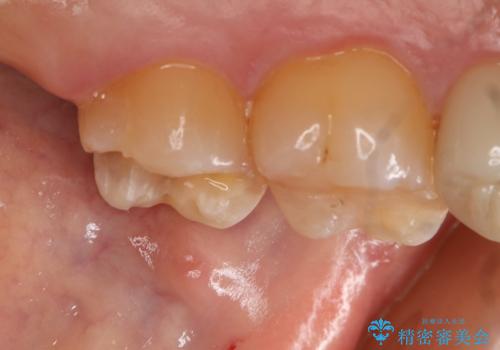

- 左上7番の銀歯のやり変えを希望された患者様です。

セラミックでの治療を希望されたため切削量などを考慮し、セラミックインレーでの治療を計画しました。

銀歯を除去し形態を整えたのち、印象しています。